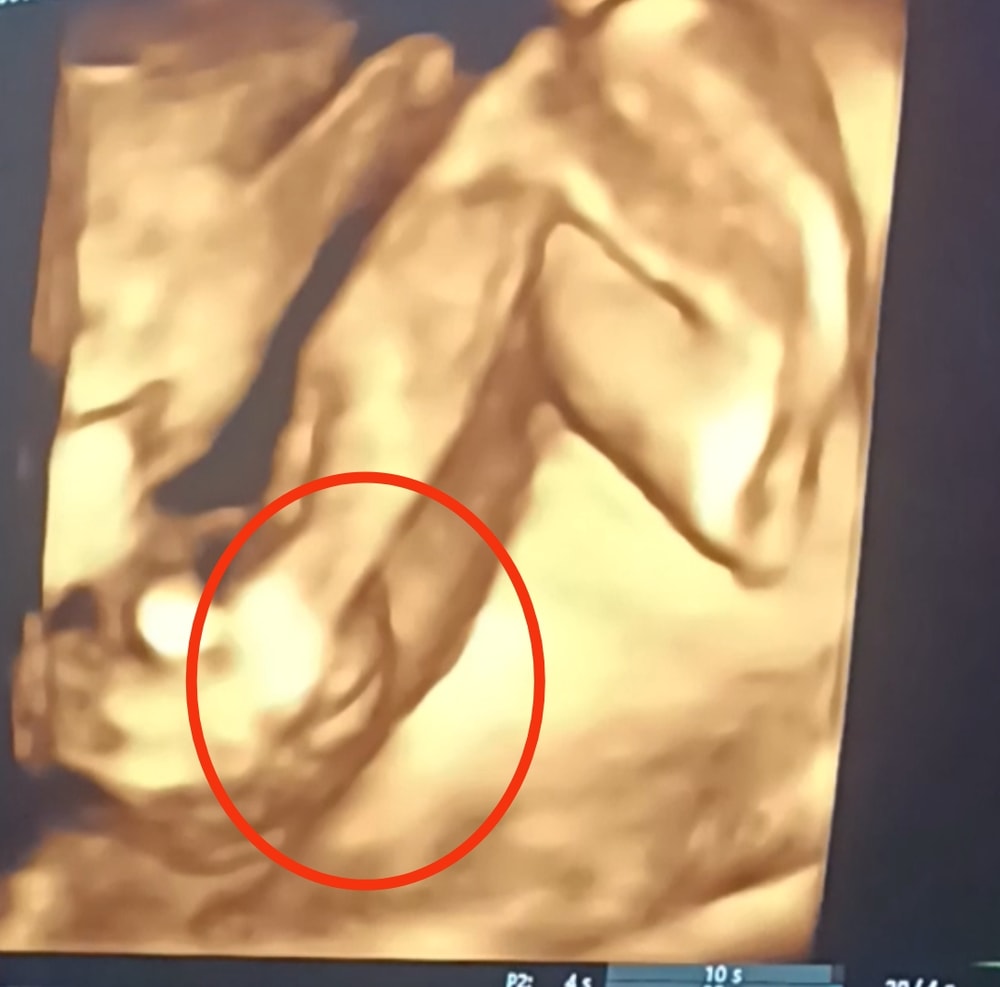

Я очень хотела девочку. И когда забеременели, я сразу решила, что девочка😂 На первом скрининге сказали, что девочка, на втором, что девочка, вчера были на 3d УЗИ на 27 недели, даже половые губы посмотрели. Мужа спрашиваю, что видишь, а он говорит, что яички. Врач посмеялась и сказала, что нет, это точно девочка. А эта мадам ещё ножки скрестила, думаю, а вдруг реально прячет и там совсем не мадама🫣

Она вообще вчера была очень стеснительна, личико спрятала, ножки скрестила. В общем, как вы считаете, девочка же, да?😂🥺 (Может немного плохо видно, она сопротивлялась нам, как могла🫣)